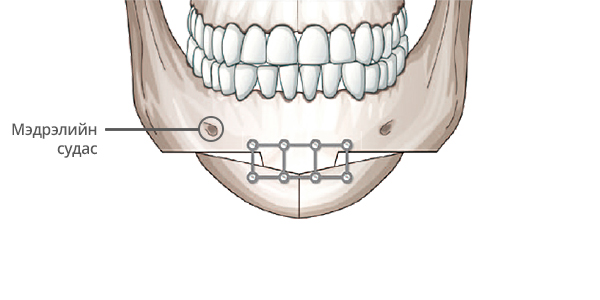

Step 1

Мэдрэлийн судсыг тойруулж, эрүүний төгсгөл хэсэгт зүсэлт хийнэ